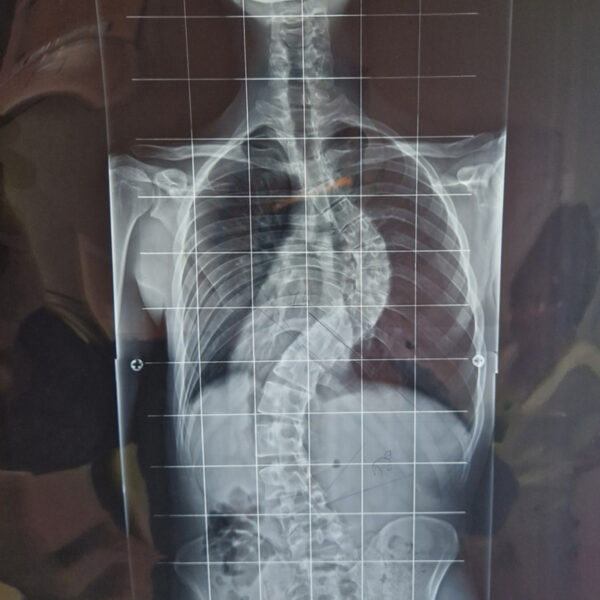

DIAGNOSI:

IPERCIFOSI DORSALE + SCOLIOSI DORSO LOMBARE

Radiografia della colonna in toto pre-operatoria

Intervento chirurgico eseguito:

STABILIZZAZIONE DORSO – LOMBARE CON OSTEOTOMIE CORRETTIVE

Radiografia della colonna in toto post-operatoria